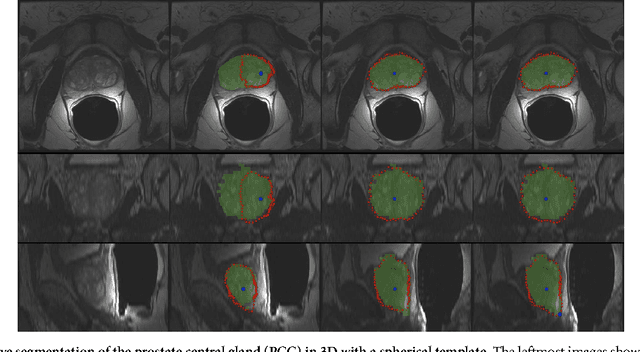

In this contribution, a semi-automatic segmentation algorithm for (medical) image analysis is presented. More precise, the approach belongs to the category of interactive contouring algorithms, which provide real-time feedback of the segmentation result. However, even with interactive real-time contouring approaches there are always cases where the user cannot find a satisfying segmentation, e.g. due to homogeneous appearances between the object and the background, or noise inside the object. For these difficult cases the algorithm still needs additional user support. However, this additional user support should be intuitive and rapid integrated into the segmentation process, without breaking the interactive real-time segmentation feedback. I propose a solution where the user can support the algorithm by an easy and fast placement of one or more seed points to guide the algorithm to a satisfying segmentation result also in difficult cases. These additional seed(s) restrict(s) the calculation of the segmentation for the algorithm, but at the same time, still enable to continue with the interactive real-time feedback segmentation. For a practical and genuine application in translational science, the approach has been tested on medical data from the clinical routine in 2D and 3D.